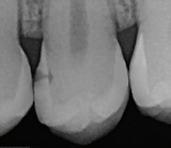

Periapical radiograph at the completion of the endodontic protocol. Resin-modified glass ionomer cement is placed as an intraradicular barrier in the distal canal, along the pulpal floor, and as an orifice barrier in the mesial canals.

In the endodontic stage, conservative endodontic preparation and obturation with modern techniques are performed as they are for any tooth. All endodontic procedures are performed under an operating microscope to maximize visualization and illumination of the fracture line (Fig 1). The coronal portion of the newly placed gutta percha is removed 2 to 3 mm below the deepest extent of the crack in the affected canal to prepare for intraradicular barrier placement (Fig 2). Gutta percha is also removed 2 to 3 mm into the other noncracked canal orifices in the tooth to prepare for traditional orifice barriers. Microscopic transillumination with a fiber-optic light, in which an LED light probe is placed against buccal or lingual tissues overlying the roots, is utilized to illuminate the root and enhance visualization of the crack (Fig 3). A flowable resin-modified glassionomer or composite resin is then placed in this newly created void from the level of the gutta percha to the floor of the pulp chamber in all canal orifices (Fig 4). A composite resin core is then placed to permanently restore the endodontic access. If a temporary or permanent crown is not placed immediately after the endodontic procedures, the tooth is reduced

resistance to fracture.30-32 Therefore, the recommendation in the protocol of placing these deep intracanal restorations maximizes both the seal internally and the fracture resistance of the root. A composite or glass ionomer core is placed after the intraradicular and orifice barriers to restore the endodontic access cavity and complete the internal seal of the crack. Posts should be avoided in cracked teeth as they decrease fracture resistance of pericervical dentin and have been linked to lower survival rates.15,27,33

Placement of a full-coverage restoration is the final step in managing these teeth. In a retrospective study, Chen et al reported a 93.6% success rate for cracked teeth restored with crowns, compared with just 20% for those that did not receive full-coverage restoration.15 They concluded that crown restoration was “the single most important factor for prognosis” of cracked teeth.15 Nguyen Thi and Jansson reported 5- and 10-year survival rates of endodontically treated cracked teeth that receive a full crown to be 97% and 95%, respectively, compared with 57% and 37%, respectively, for teeth that were restored with a composite resin crown or filling.34 Therefore, crown placement is highly predictive of both success and survival in cracked teeth.